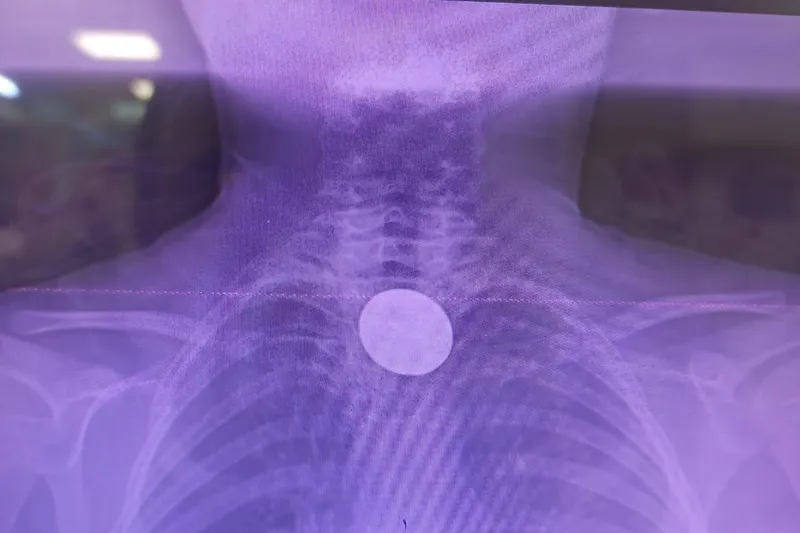

Yapılan incelemelerde 5 TL’lik madeni paranın Y.K.’nin yemek borusuna kadar ilerlediği belirlendi. Çocuk hastalarda ciddi solunum ve sindirim sistemi riskleri oluşturabilen bu durum üzerine ilgili branşlar vakit kaybetmeden harekete geçti.

Madeni paranın çıkarılması için Gastroenteroloji Uzmanı Dr. Yaren Dirik ile Kulak Burun Boğaz (KBB) Hekimi Dr. Yasin Gökçınar tarafından ortak bir girişim gerçekleştirildi. Alanında uzman ekiplerin koordineli çalışmasıyla madeni para herhangi bir komplikasyona yol açmadan başarıyla çıkarıldı.